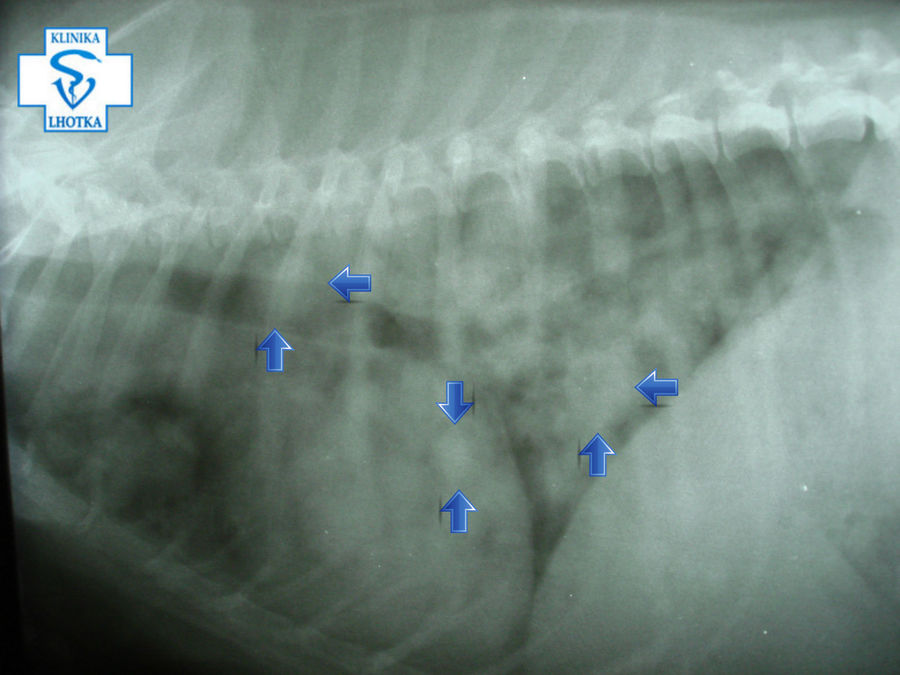

Tato vyšetření nám bohužel odhalila četné metastáze v plicích i na orgánech v dutině břišní.

Na rentgenogramech jsou šipkami označeny některé z mnohočetných kulovitých metastáz v plicích způsobujících dechové potíže.